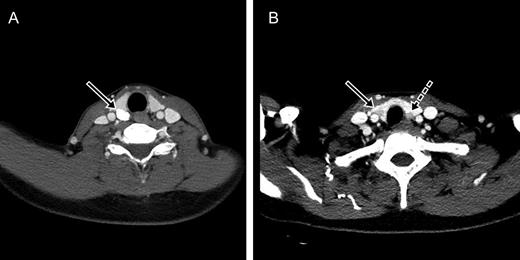

In the preoperative evaluation, two-hour-delayed 99mTc-sestamibi scintigraphy showed increased uptake in both inferior parathyroid glands (Fig. 2). Computed tomography (CT) of the neck showed a calcified nodule posterior to the right superior thyroid gland, a solid nodule in the right lower thyroid gland and an enlarged parathyroid gland posterior to the left inferior thyroid (Fig. 3). Sonography (SONO) showed a benign-looking nodule in the right lower thyroid and two adjoining enlarged parathyroid glands posterior to the left lower thyroid (Fig. 4). The right mid-thyroid nodule appeared benign, and a fine-needle aspiration biopsy was not performed. The right inferior parathyroid gland could not be identified in the CT or SONO findings. During neck exploration, four oval masses similar to parathyroid glands were observed (right superior: 1.7 × 1.0 cm, right inferior: 0.5 × 0.3 cm, left superior: 1.0 × 0.7 cm, left inferior: 0.8 × 0.6 cm). The left inferior parathyroid gland was partially preserved, while the other lesions were completely removed. Intraoperative frozen biopsy of the four masses revealed two cases of parathyroid hyperplasia, a parathyroid hyperplasia with a calcified nodule in the right superior area and a lymph node in the right inferior area. The right inferior parathyroid was not found during right neck exploration.

Parathyroid glands and the thyroid nodule on computed tomography. (A) A calcified nodule posterior to the right superior thyroid (arrow). (B) A solid nodule in the right lower thyroid gland (arrow) and an enlarged parathyroid gland posterior to the left inferior thyroid (dotted arrow).